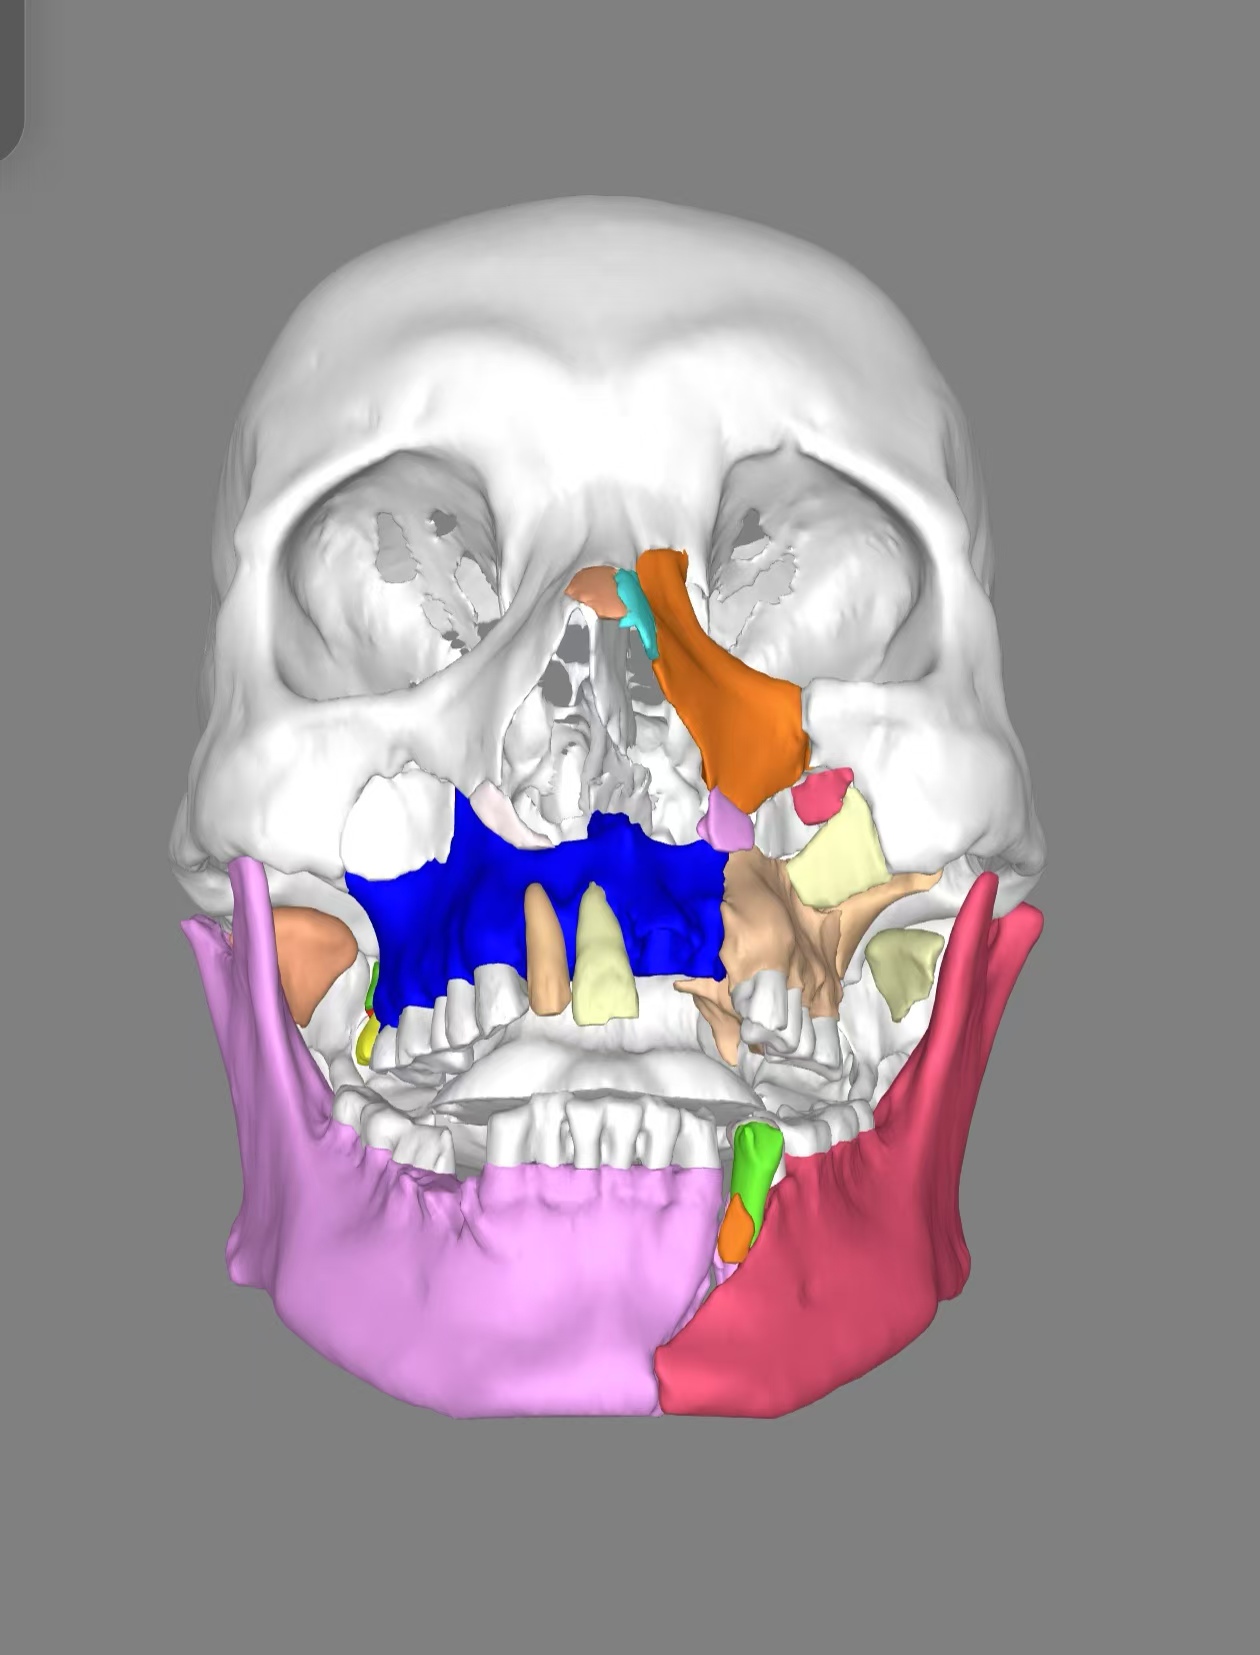

借助该模型,让团队能够在术前精准模拟手术过程,详细规划骨折复位路径和内固定方案、提前进行内固定物的预制,大大提高了手术的精准性与安全性。在充分准备后,团队在主任医师胡沛与副主任医师马莉共同带领下为姬先生成功实施了陈旧性双侧上颌骨骨折切开复位内固定术、陈旧性创伤性腭裂、陈旧性双侧髁状突骨折切开复位内固定术、陈旧性下颌骨骨折切开复位内固定术,同时还利用患者的骨折部位,纠正了患者受伤前的上颌前突、开??畸形。历经八小时,手术过程顺利,术后姬先生恢复状况良好。

术后